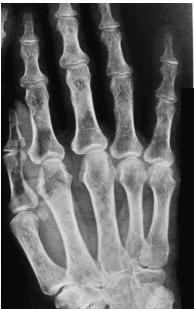

- Sub-periosteal resorption: middle phalanges, tibial shaft

- In hand, sub-periosteal bone resorption .This change usually happen in the middle phalanges, radial aspect in the 2nd or 3rd finger.

- Terminal tuft erosion.

Sub-periosteal bone resorption

- Most useful sign

- Virtually Diagnostic

- Location

Subperiosteal bone resorption (straight arrow), resorption of the tip of the terminal phalanx and the altered bone architecture. Arterial calcification is also present (curved arrow).